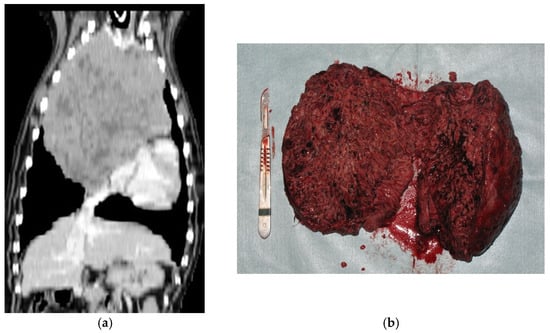

- Diagnostics: contrast-enhanced CT of the thorax without an angiogram was performed and available in 18 dogs; in older cases, medical records only reported three-view thoracic radiographs and thoracic ultrasounds for guidance in FNA of the mediastinal mass.